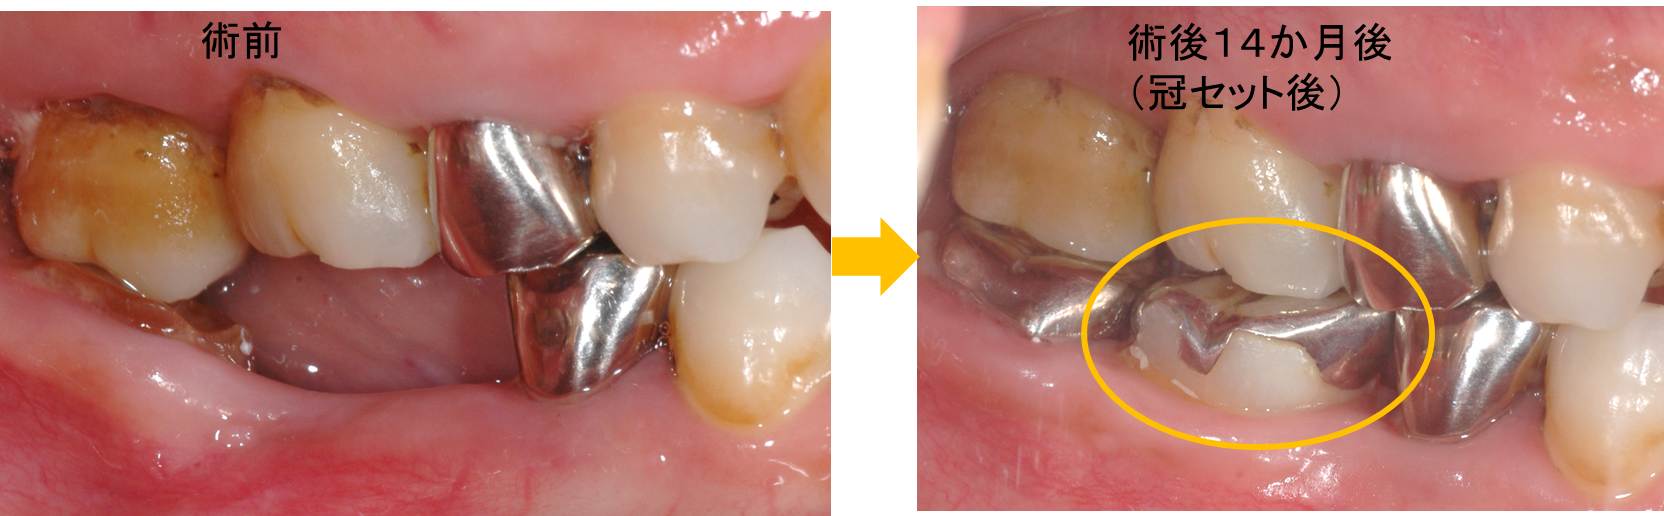

移植した親知らずのレントゲン像を見ていきます。

左写真から術前→移植直後→移植14か月後です。

また、今回の移植は「歯の神経」が術後も生きていました。ほとんどの場合は、移植後に歯の神経が死んでしまい根管治療が必要になりますが、今回は神経が生きていたため根管治療を行う必要はありませんでした。